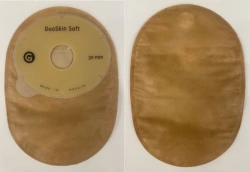

Medical product is intended for use in colostomies, ileostomies and urostomies for hermetic and secure attachment of stoma bags to the skin of the anterior abdominal wall, as well as to protect the skin of the peristomal area from stoma secretions and preserve the physiological functions of the skin due to the absorption of natural skin moisture (sweat, sebum).